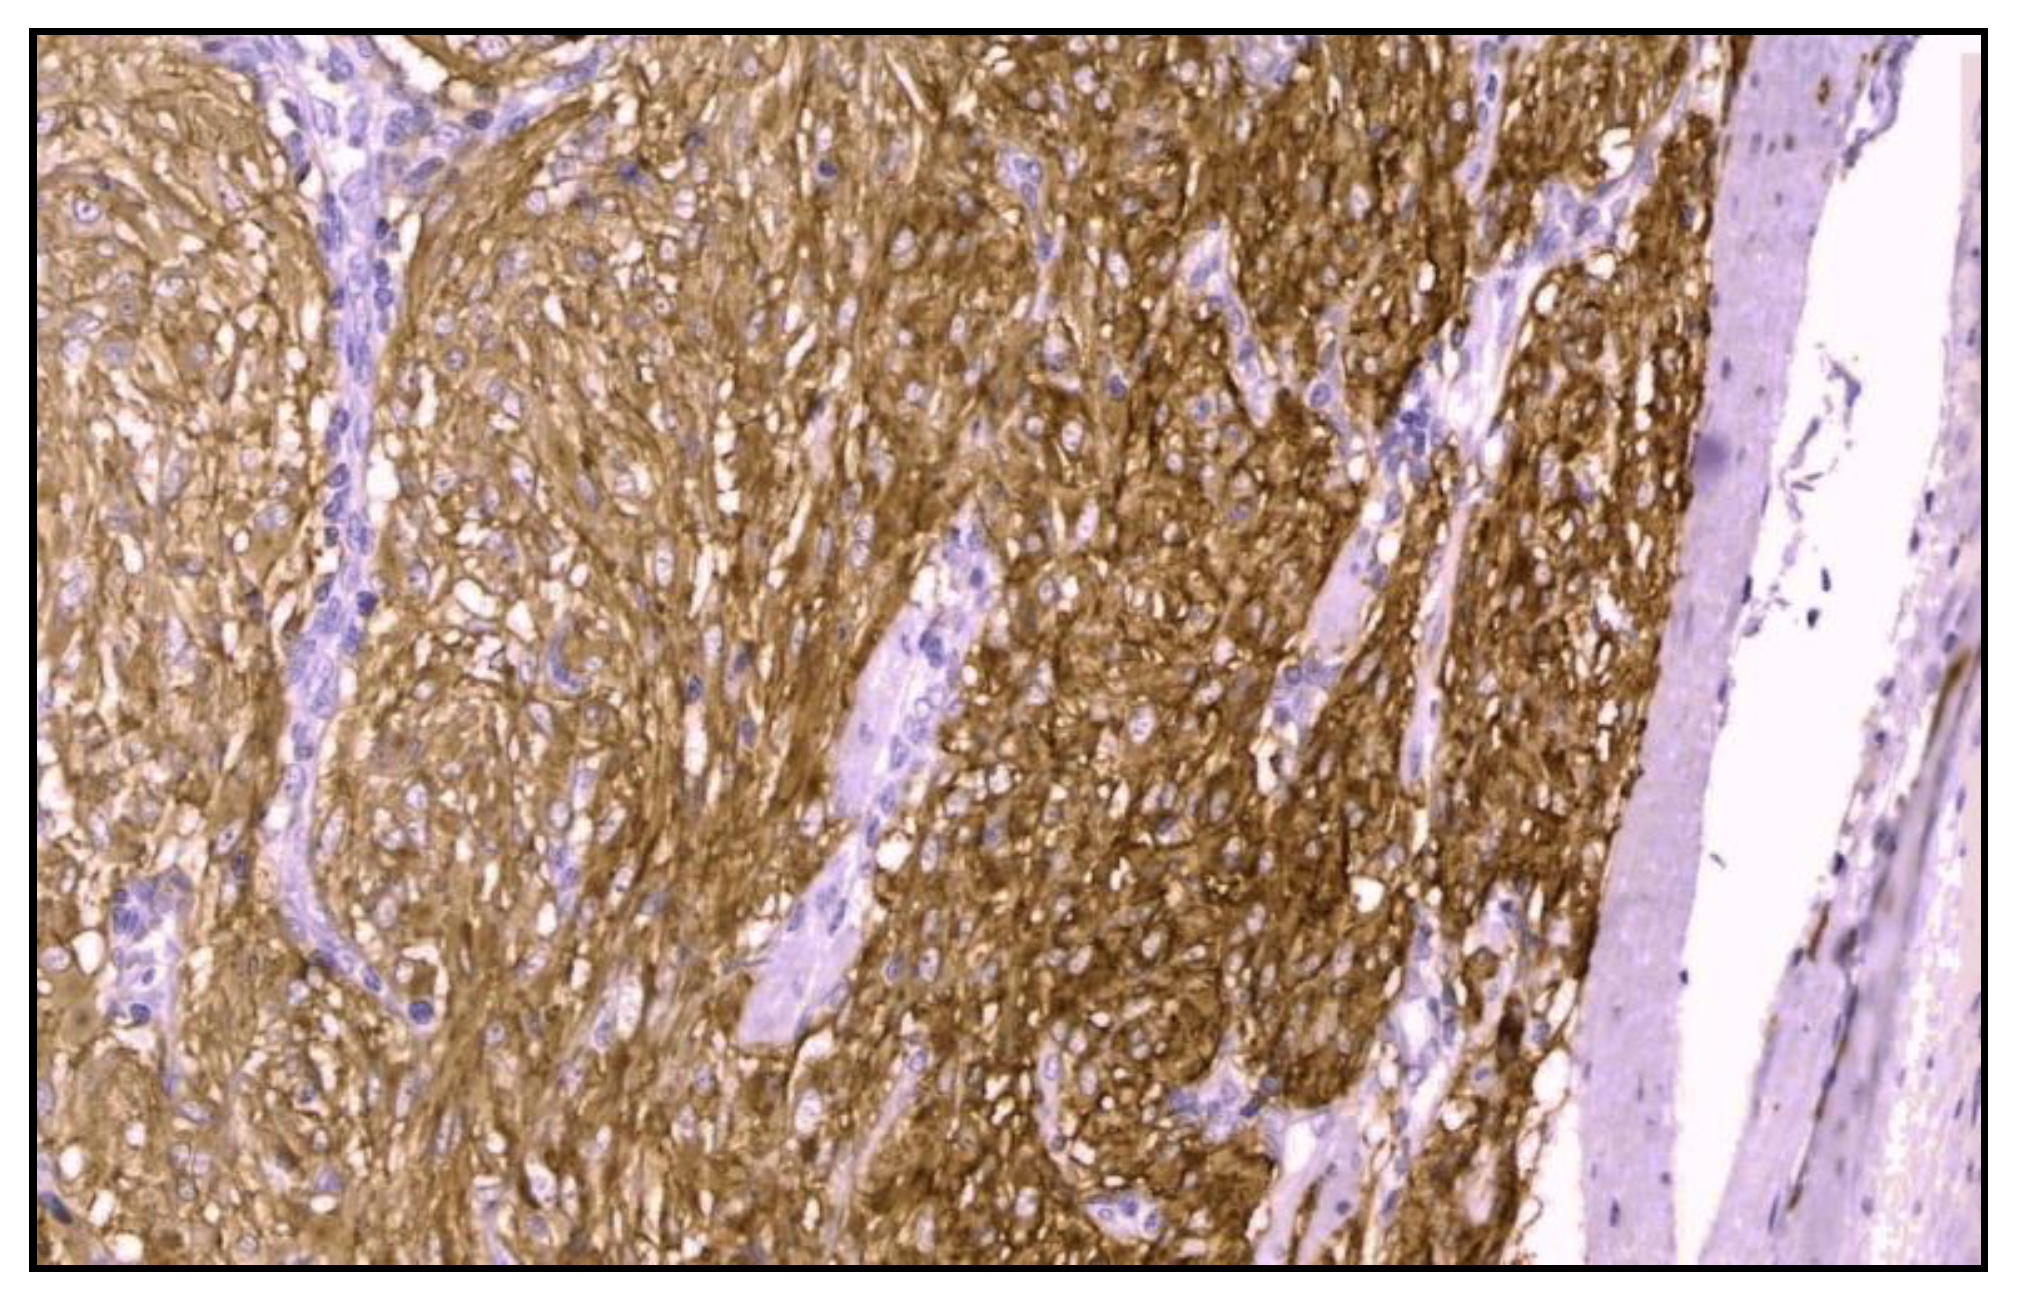

Immunohistochemistry was positive for CD117/c-kit and CD34 immunomarkers (Figure 6) and negative for desmin, vimentin, muscle-specificactin, smooth muscle actin, S-100protein and neuron-specific enolase.

Figure 6.

Microscopic finding immunohistochemistry exhibiting a strong positive for CD117 (CD117 staining; optical magnification of 40x).